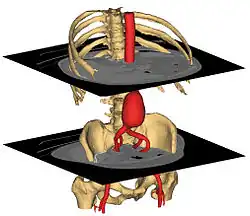

3D surface models created in Mimics from CT | |

Materialise Mimics is an image processing software for 3D design and modeling, developed by Materialise NV,[1] a Belgian company specialized in additive manufacturing software and technology for medical, dental and additive manufacturing industries. Materialise Mimics is used to create 3D surface models from stacks of 2D image data. These 3D models can then be used for a variety of engineering applications. Mimics is an acronym for Materialise Interactive Medical Image Control System. It is developed in an ISO environment with CE and FDA 510k premarket clearance. Materialise Mimics is commercially available as part of the Materialise Mimics Innovation Suite, which also contains Materialise 3-matic, a design and meshing software for anatomical data. The current version is 24.0(released in 2021), and it supports Windows 10, Windows 7, Vista and XP in x64.

Materialise Mimics calculates surface 3D models from stacked image data such as Computed Tomography (CT), Micro CT, Magnetic Resonance Imaging (MRI), Confocal Microscopy, X-ray and Ultrasound, through image segmentation. The ROI, selected in the segmentation process is converted to a 3D surface model using an adapted marching cubes algorithm that takes the partial volume effect into account, leading to very accurate 3D models.[2][3] The 3D files are represented in the STL format.

-

Image import from CT (DICOM)

-

Image segmentation

-

3D model

3D model